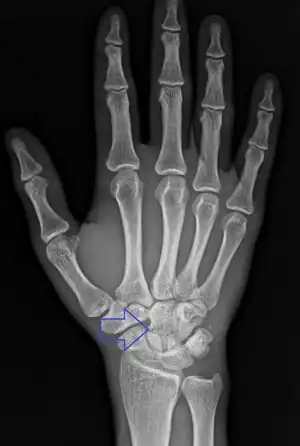

Diagnosis

Diagnosis is often by a posterior anterior wrist X-ray.[2]